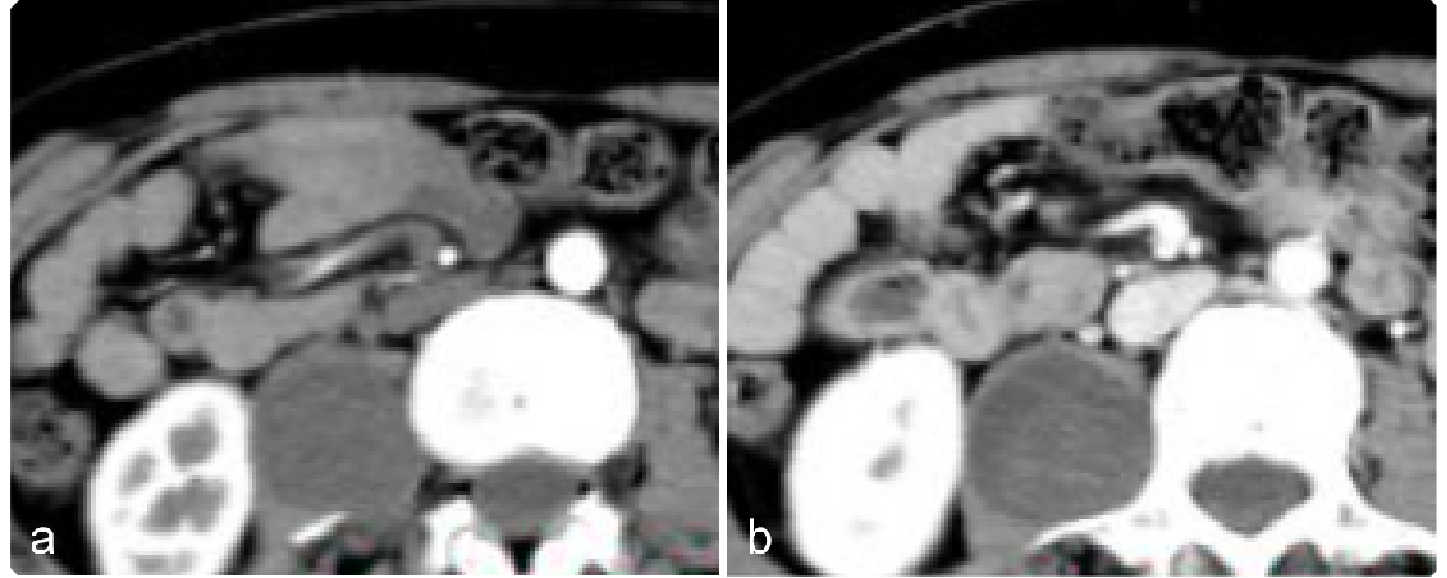

47df5e91be9763c0283a82cb0256446c.png 病例 23:(盆腔内)神经鞘瘤  46岁女性,因发现腹部肿块10余年,腹部隐痛1月余,实验室检查无特殊a1-a4为横断位多个层面;b1-b2为冠状位两个层面;c1-c2为矢状位两个层面;d为动脉和肿瘤的三维成像。肿瘤可见包膜,瘤体可见明显囊变坏死。免疫组化:S-100(+)、SOX-10(+)、CD117(-)、Dog-1(-)、 SMA(-)、Ki-67 (+,<1%)。特殊染色:PAS、网染无特殊。

309da72b651fad69b53c1ea5f4ca297c.png 病例 24:(腹膜后)神经鞘瘤囊变  41岁女性,偶然发现腹部肿块(a) CT增强显示低密度肿块,内见线样钙化(箭)。(b) T2WI-FS显示肿块呈不均匀高信号,内见囊变区形成(*)。(c) 大体病理显示肿瘤界限清楚,具有棕黄色实性和囊性切面(箭),其中60%为白色纤维组织,40%为黄色脂肪组织。中央为出血性囊性成分(*)。(d) 镜下显示中央囊肿(*)及周围更小的囊肿(箭)(HE×40)。(e) 高倍镜显示由栅栏样细胞(箭头)组成的Verocay小体,这些细胞被低细胞透明化区域(*)隔开(HE×200)。